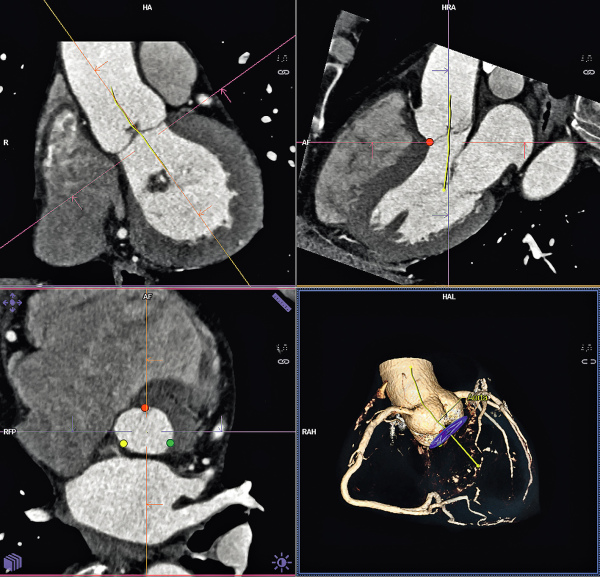

Abbildung 1: Produkt: TAVI Vertrieb: Siemens AG syngo.CT Cardiac Function-Valve Pilot |

Abbildung 1: Produkt: TAVI

Vertrieb: Siemens AG syngo.CT Cardiac Function-Valve Pilot |